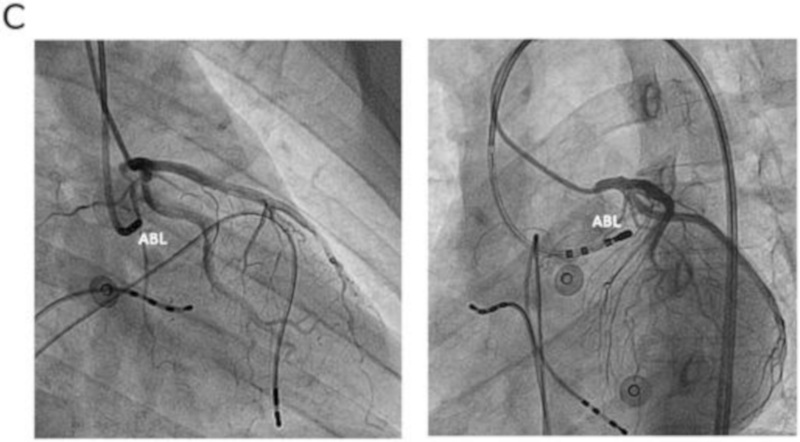

Distance from coronaries

cor_angio.jpg

lad_too_close.jpg